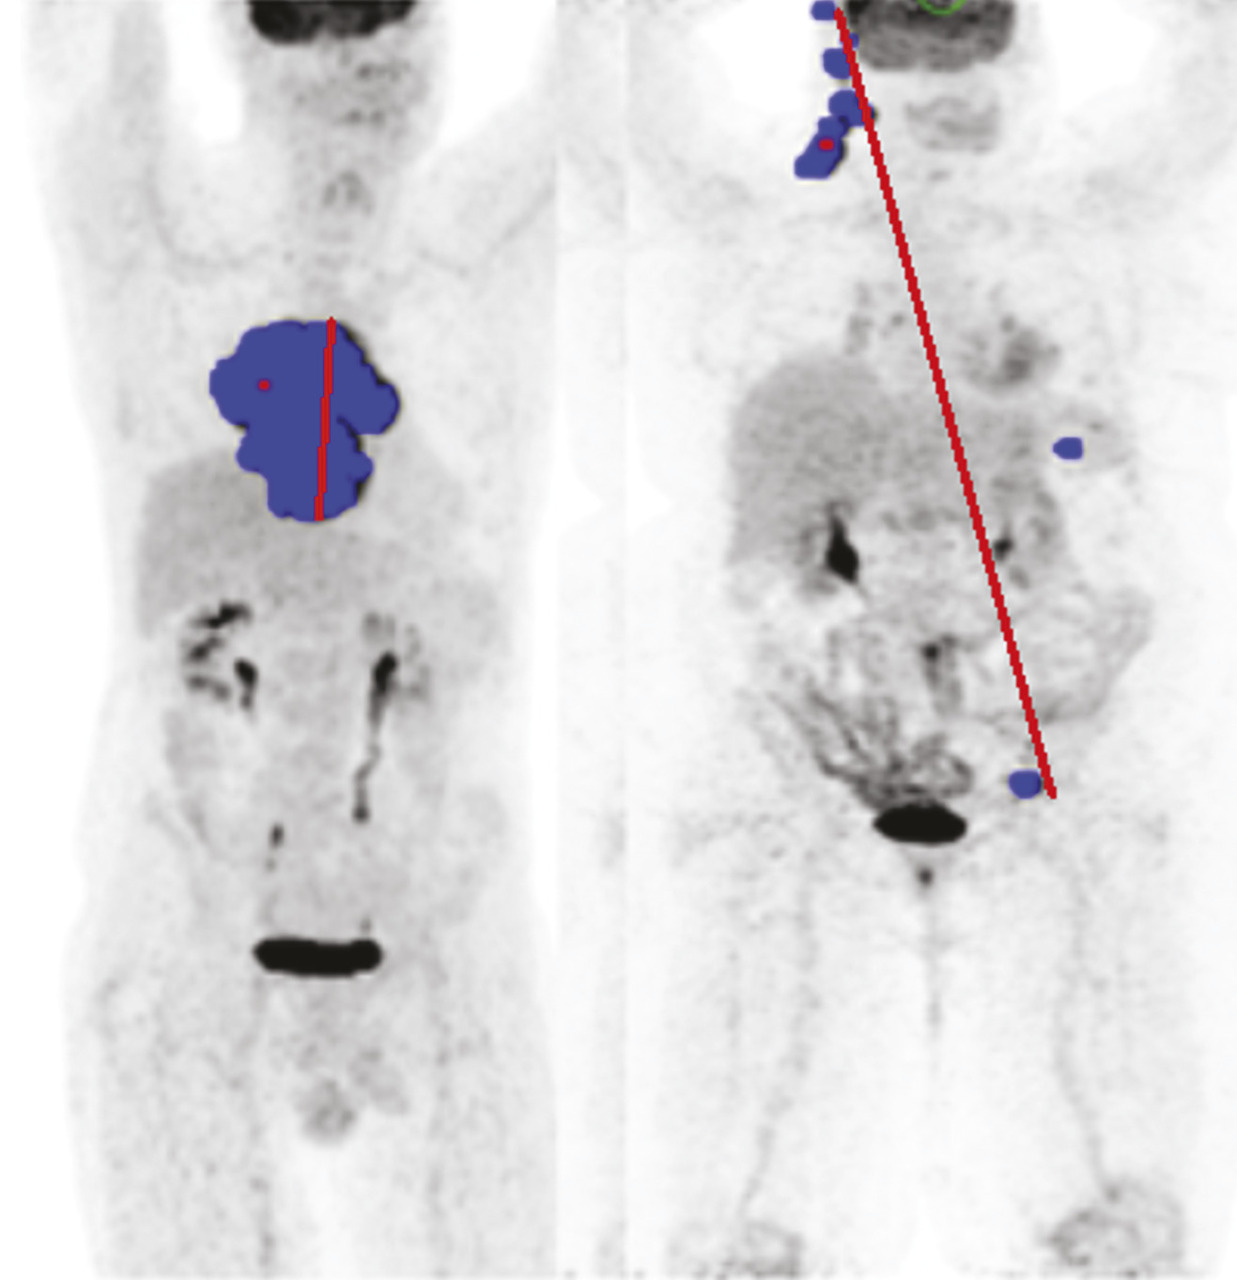

Dmax, un indice pronostique additionnel

Plus récemment, la mesure de la dispersion des lésions, toujours sur le TEP initial, a été proposée comme facteur pronostique indépendant, en plus du TMTV et de la réponse à deux cycles. Ce nouvel indice appelé Dmax (distance maximale) mesure la distance entre les deux atteintes les plus éloignées. Ce paramètre est, dans l’esprit, une version quantifiée du stade d’Ann Arbor et constitue un indice pronostique additionnel pouvant être extrait des TEP de baseline (fig. 3 ).10

Plus généralement, ces nouveaux paramètres, appelés radiomics, sont des descripteurs quantifiés de la maladie et vont probablement constituer les futurs apports de la TEP pour identifier plus finement les groupes pronostiques de patients et construire des protocoles de traitement de plus en plus personnalisés.